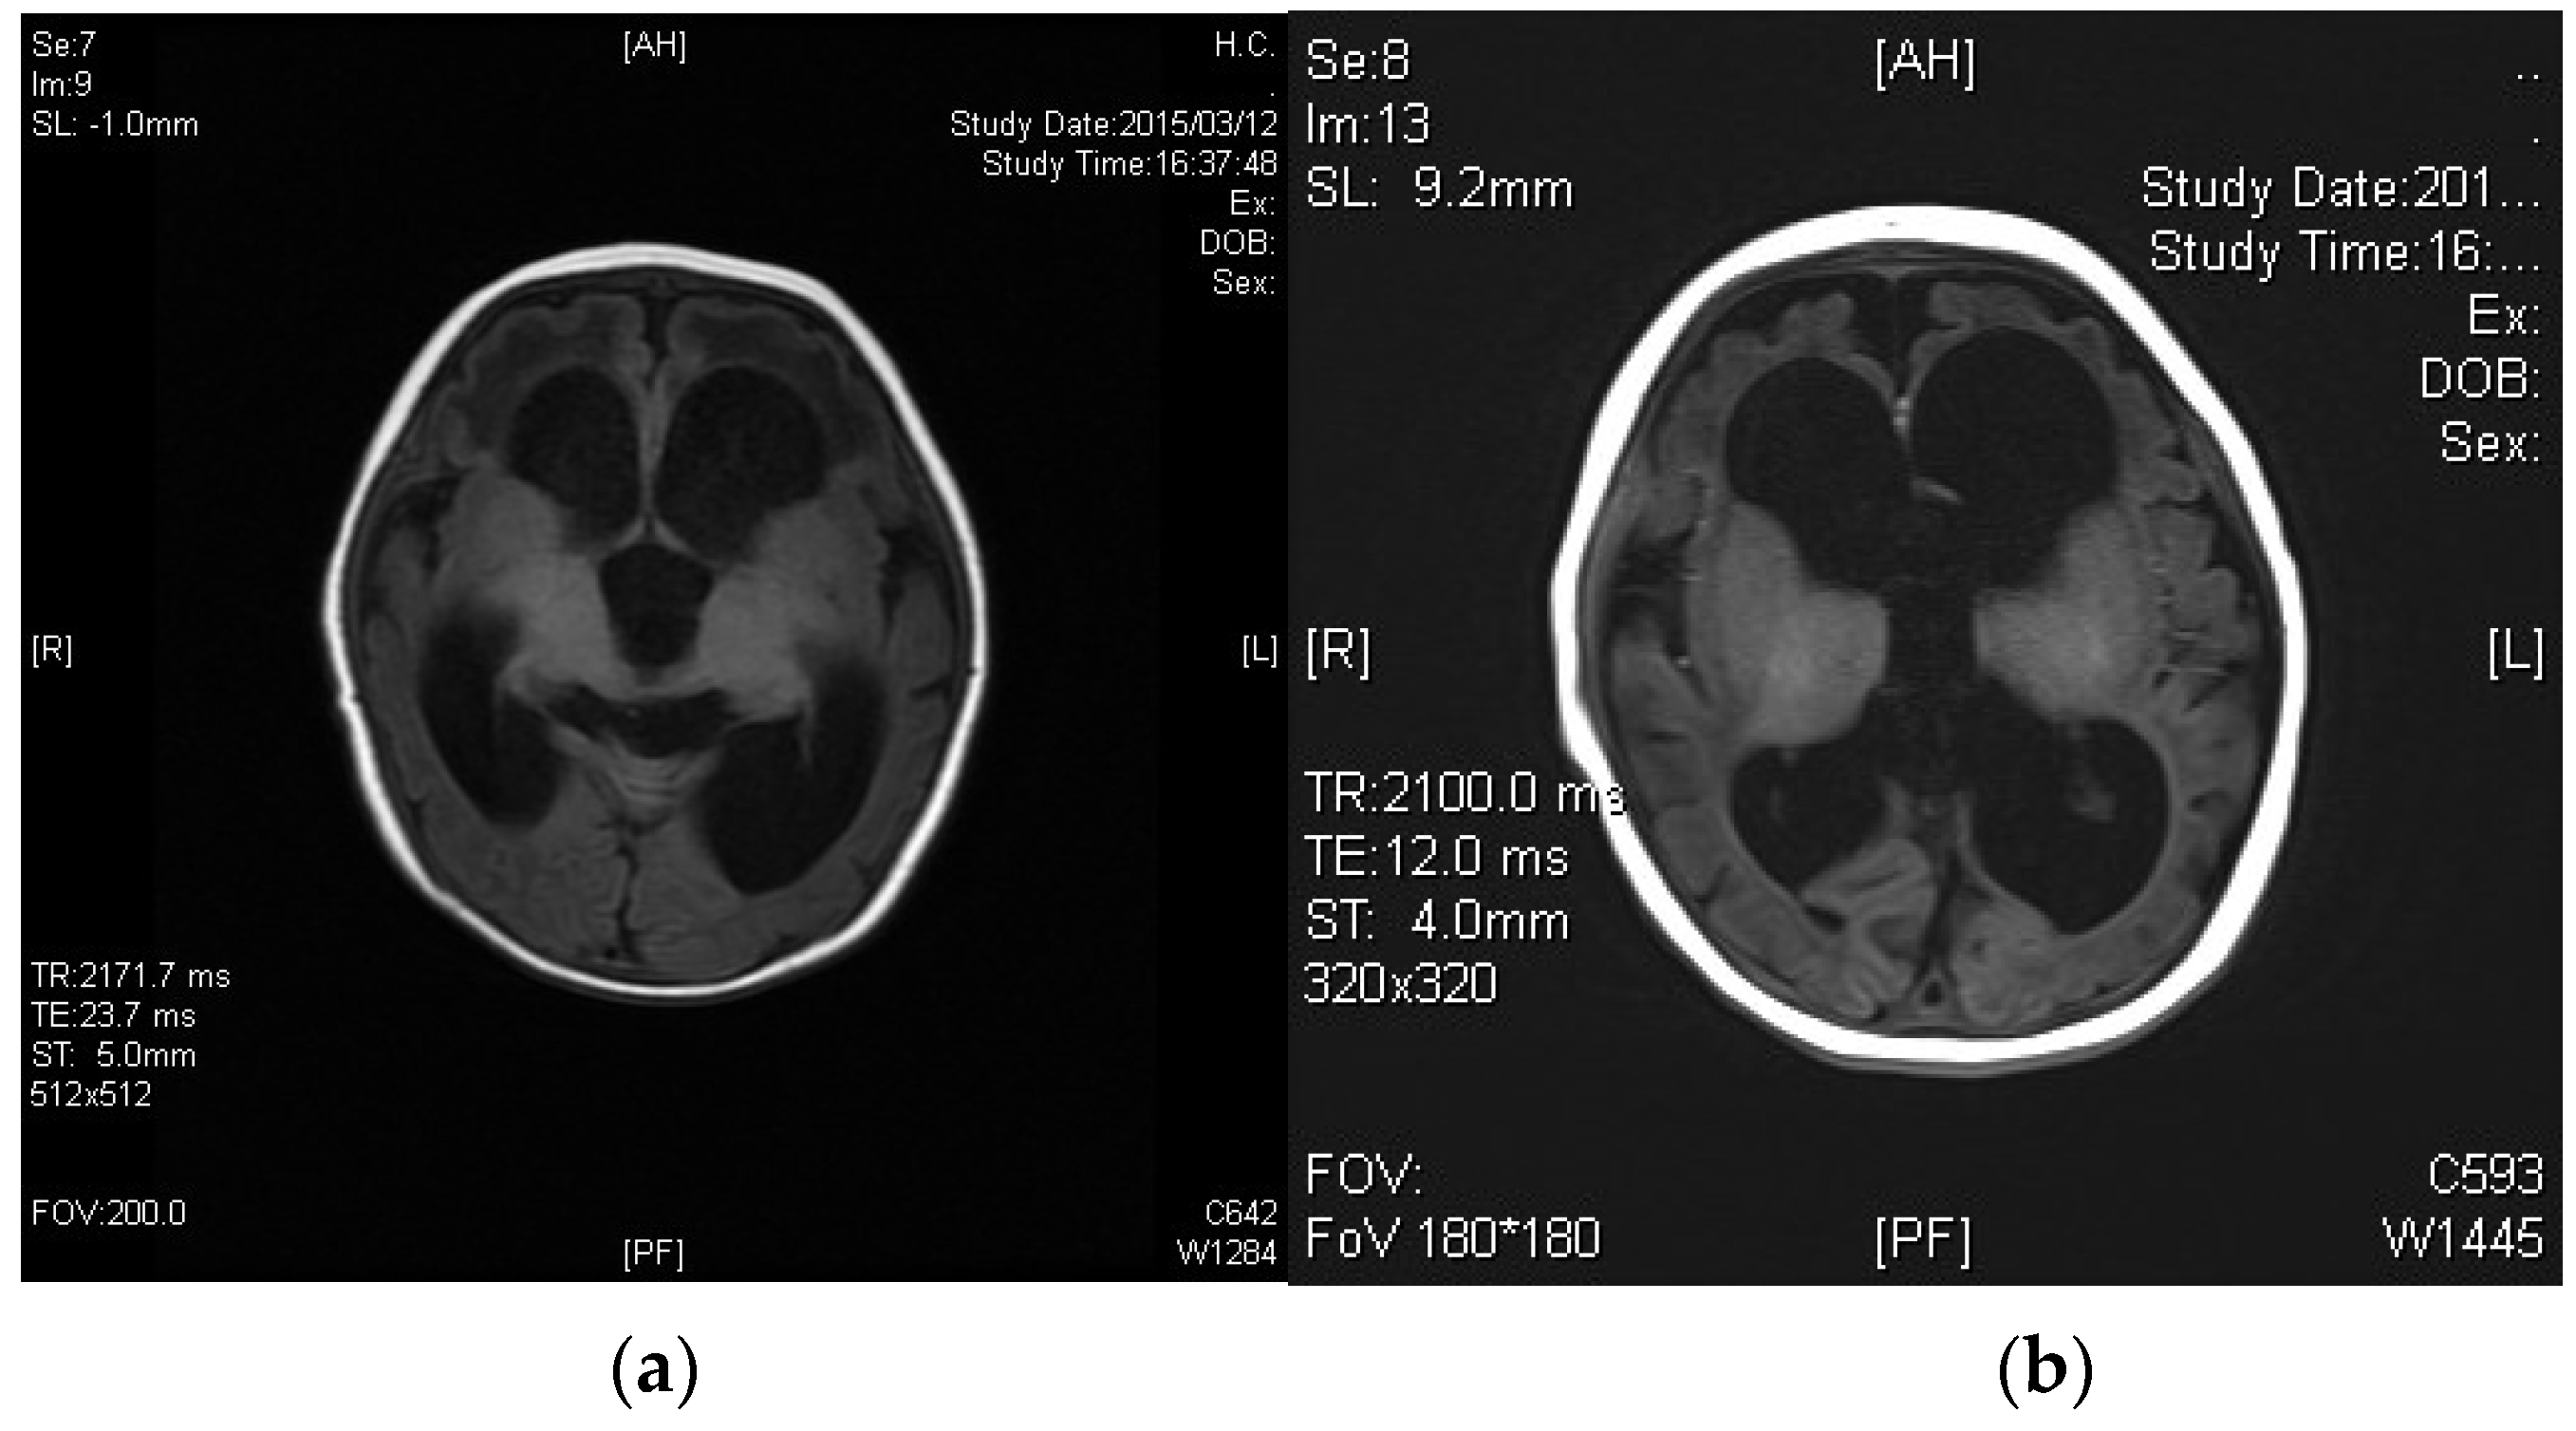

3.1. Case 1

3.2. Case 2

3.3. Case 3